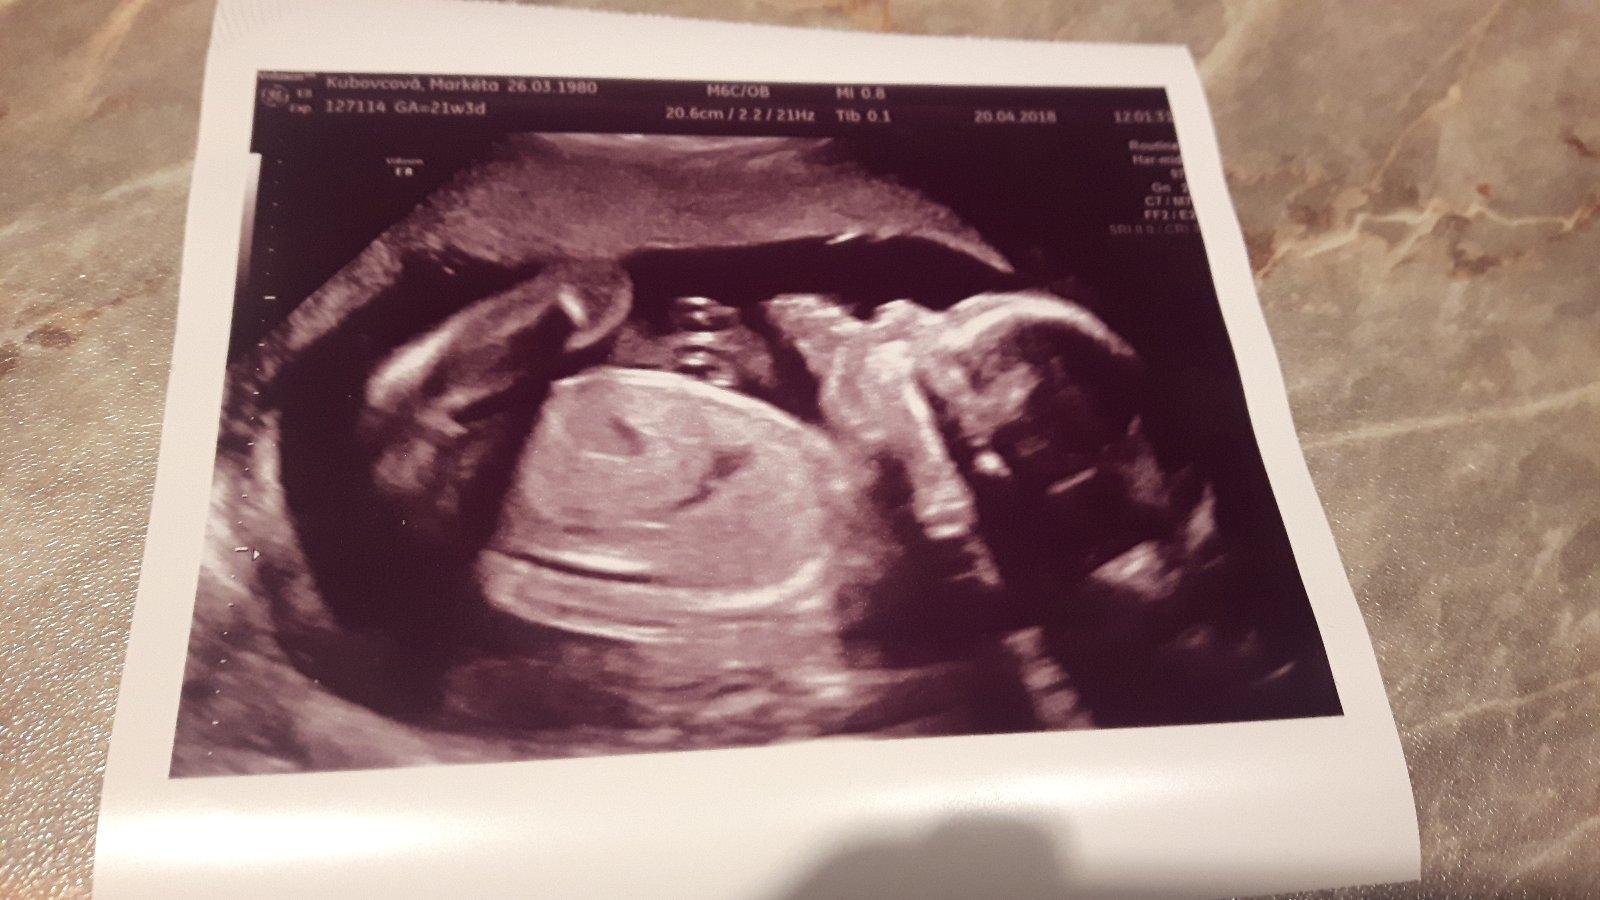

@rosalline Ahojky jak se mas?Jak se vam dari?Uz vis co budete mit?My se dneska dozvedely ze c3kame chlapecka.Ale ne na velkym utz ale jen u gyndarky.Ale rikala ze je to jasny.😊😊

@natysnovec ahoj, to jsem ráda, že se vám dobře daří. Taky máme kluka..:o).

@rosalline my mame taky kluka

Take kluk! 😁